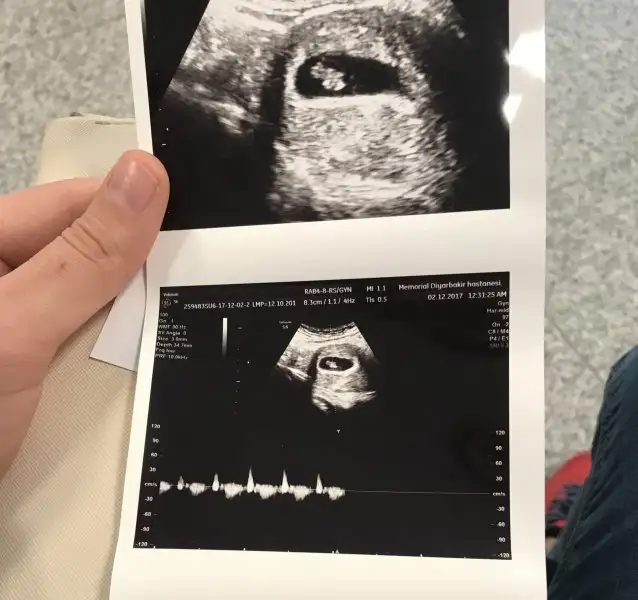

bebegin7-8 haftalıkkenki usg resimine direkt baktıgınızda;

bebek kesenin soluna yakınsa bebek erkek,

sagına yakınsa kız.

Mrb bende 9haftalık hamilymBu yöntem bircok kişide dogru sonuc verdii.

Biri 7 hafta 1 günlük biri 11 haftalık şuan 13 haftalık oldum acaba cinsiyeti ne olabilir tahmin de bulunabilir misiniz acaba Haftaya da doktora gidip net bi şekilde öğrenicem inşallah[/QU